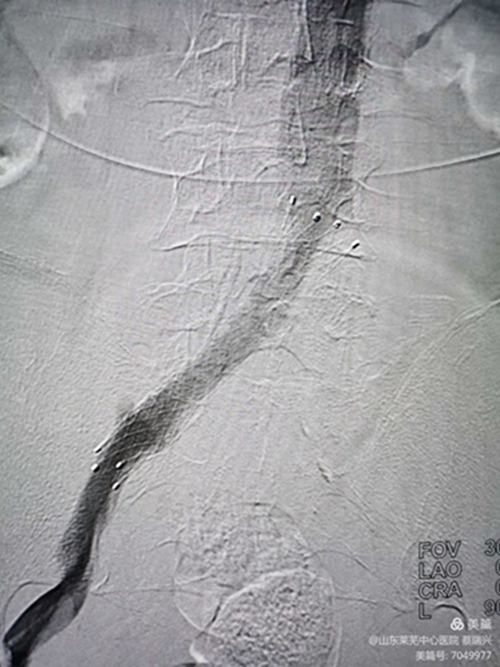

男性,81歲,左下肢腫脹4天入院,行走不至百米,疼痛,便要休息,嚴(yán)重功能障礙。左下肢I(xiàn)II度水腫,脹力高。腳踝部有淤血斑。彩超示,左下肢深靜脈諸段屬支血流通暢,速度慢。髂總靜脈觀察不清。認(rèn)為還是髂總有問題,行造影。取左腘靜脈入路,造影證實(shí)左髂總靜脈閉塞,開通后留置溶栓導(dǎo)管4天。給予左髂總靜脈支架成形術(shù)。溶栓導(dǎo)管造影證實(shí),左髂總?cè)杂兄囟泉M窄,血流不暢,易再閉。

閉塞前改變

支架置入后,行后擴(kuò)張,閉塞部位球囊成形,有"腰征",且擴(kuò)張阻力大,說明是閉塞,且已閉塞很長時(shí)間。(如是壓迫或新閉塞,支架自行成形好,一般不用后擴(kuò)。)